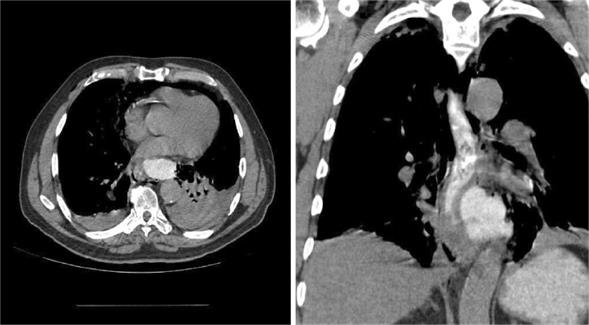

Hombre 63 años, ex fumador, hipertenso. Luego de ingesta copiosa, presenta vómitos profusos e intensa epigastralgia acompañada de edema facial, consultando en centro secundario. Se constata enfisema subcutáneo en cara, cuello y tórax con radiografía de tórax que muestra neumomediastino, trasladándose a emergencia del Hospital Maciel. Ingresa vigil, dolorido, apirético, estable en lo hemodinámico y respiratorio. Electrocardiograma con taquicardia sinusal sin elementos de isquemia aguda. De la paraclínica se destaca: glóbulos blancos de 18.000/mm3; resto incluido troponinas sin alteraciones. Valorado por cirujano solicita tomografía computarizada (TC) cuello, tórax y abdomen que informa: enfisema subcutáneo de distribución simétrica en sector cervical, a nivel torácico enfisema mediastinal extendido a región paracardíaca disecando espacios peritraqueales, periesofágicos y periaórticos. Cerca del hiatus colección con nivel hidroaéreo. Derrame pleural bilateral mayor a izquierda. Mediante contraste hidrosoluble vía oral (VO), se observa colección paraesofágica izquierda, sin pared propia, de 5 x 6 cm, probablemente relacionada a fuga de contraste (figura 1).

Figura 1: Tomografía computada de tórax con contraste vía oral. Se observa fuga de contraste con colección paraesofágica izquierda. Derrame pleural bilateral mayor a izquierda donde produce atelectasia pasiva del lóbulo inferior izquierdo. En el corte frontal se observa la topografía de la perforación a nivel del tercio inferior del esófago a izquierda.